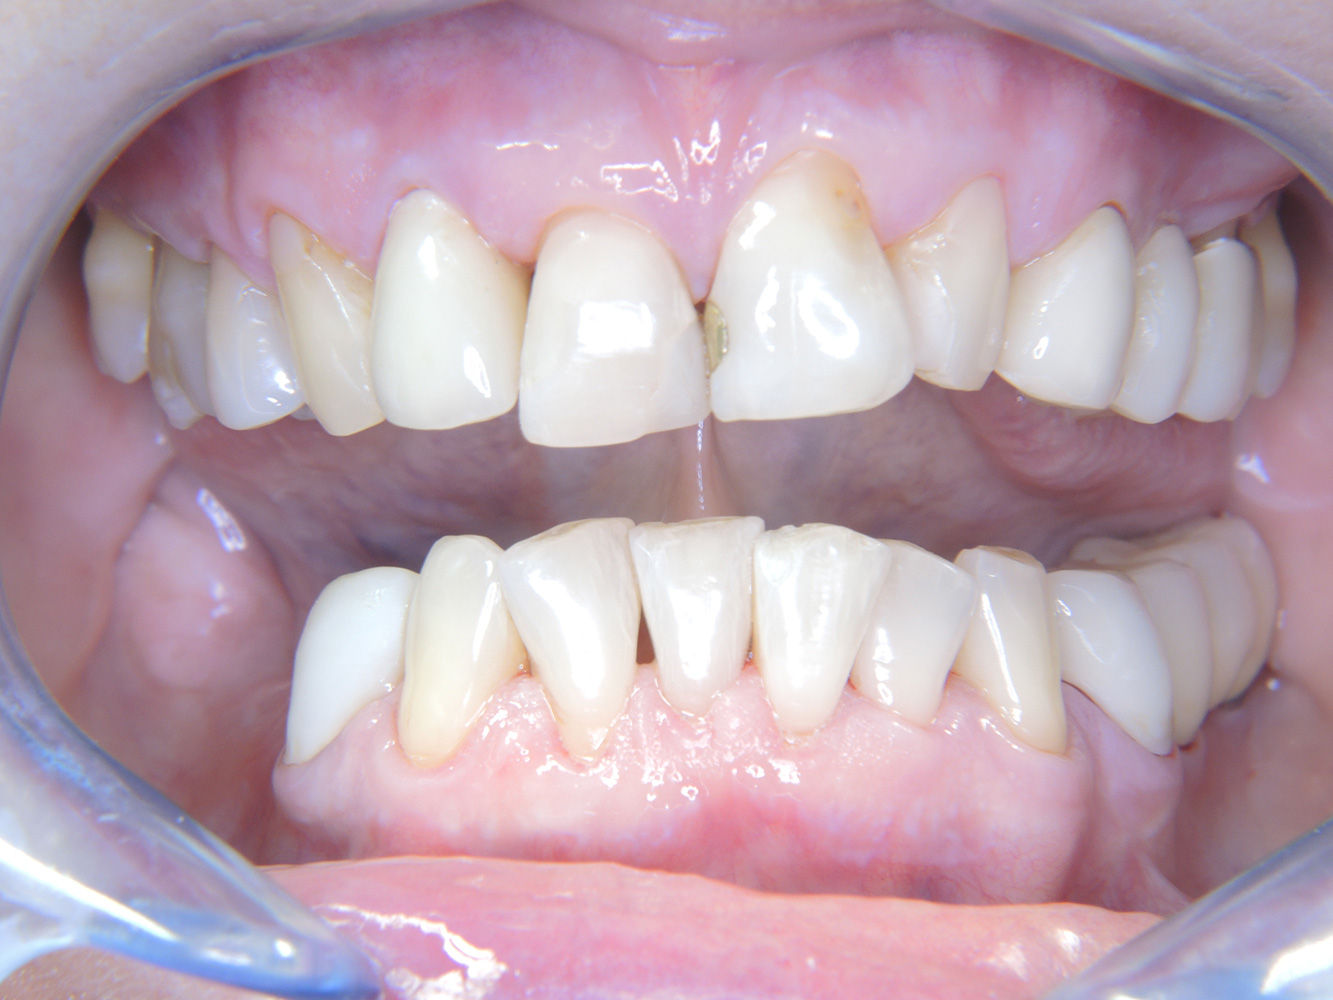

Die 68-jährige Patientin hat keine zahnmedizinisch relevanten allgemeingesundheitlichen Vorerkrankungen oder Medikation, auch aus dem Lebensstil ergibt sich kein besonderes Risiko. Die Patientin hat zwei Implantate (3. Quadrant, seit fünf Jahren) sowie eine parodontale Vorerkrankung (Parodontitis Stadium IV, Grad B) mit Zahnverlust. Derzeit zeigen sich stabile parodontale Verhältnisse. Für die Prophylaxesitzung ergeben sich vier Empfehlungen in den Bereichen Anamnese/Befund, Motivation/Instruktion, der Wahl der geeigneten Instrumente und für Resümee/Folgetermin.

Da die Patientin keine besonderen Risikofaktoren mit spezifischen zahnmedizinischen Auswirkungen hat, ist der aus der Mundgesundheit ermittelte Bedarf maßgebend. Hier ist einmal jährlich ein ausführlicher Parodontalstatus empfohlen. So kann rechtzeitig auf eine mögliche Progression der parodontalen Vorerkrankung oder die Entstehung einer Periimplantitis reagiert werden.

Aufgrund der Implantatsituation mit parodontaler Vorerkrankung hat die Patientin ein Entstehungsrisiko für eine Periimplantitis – empfohlen wird eine Wiedervorstellung im Intervall von drei bis vier Monaten.